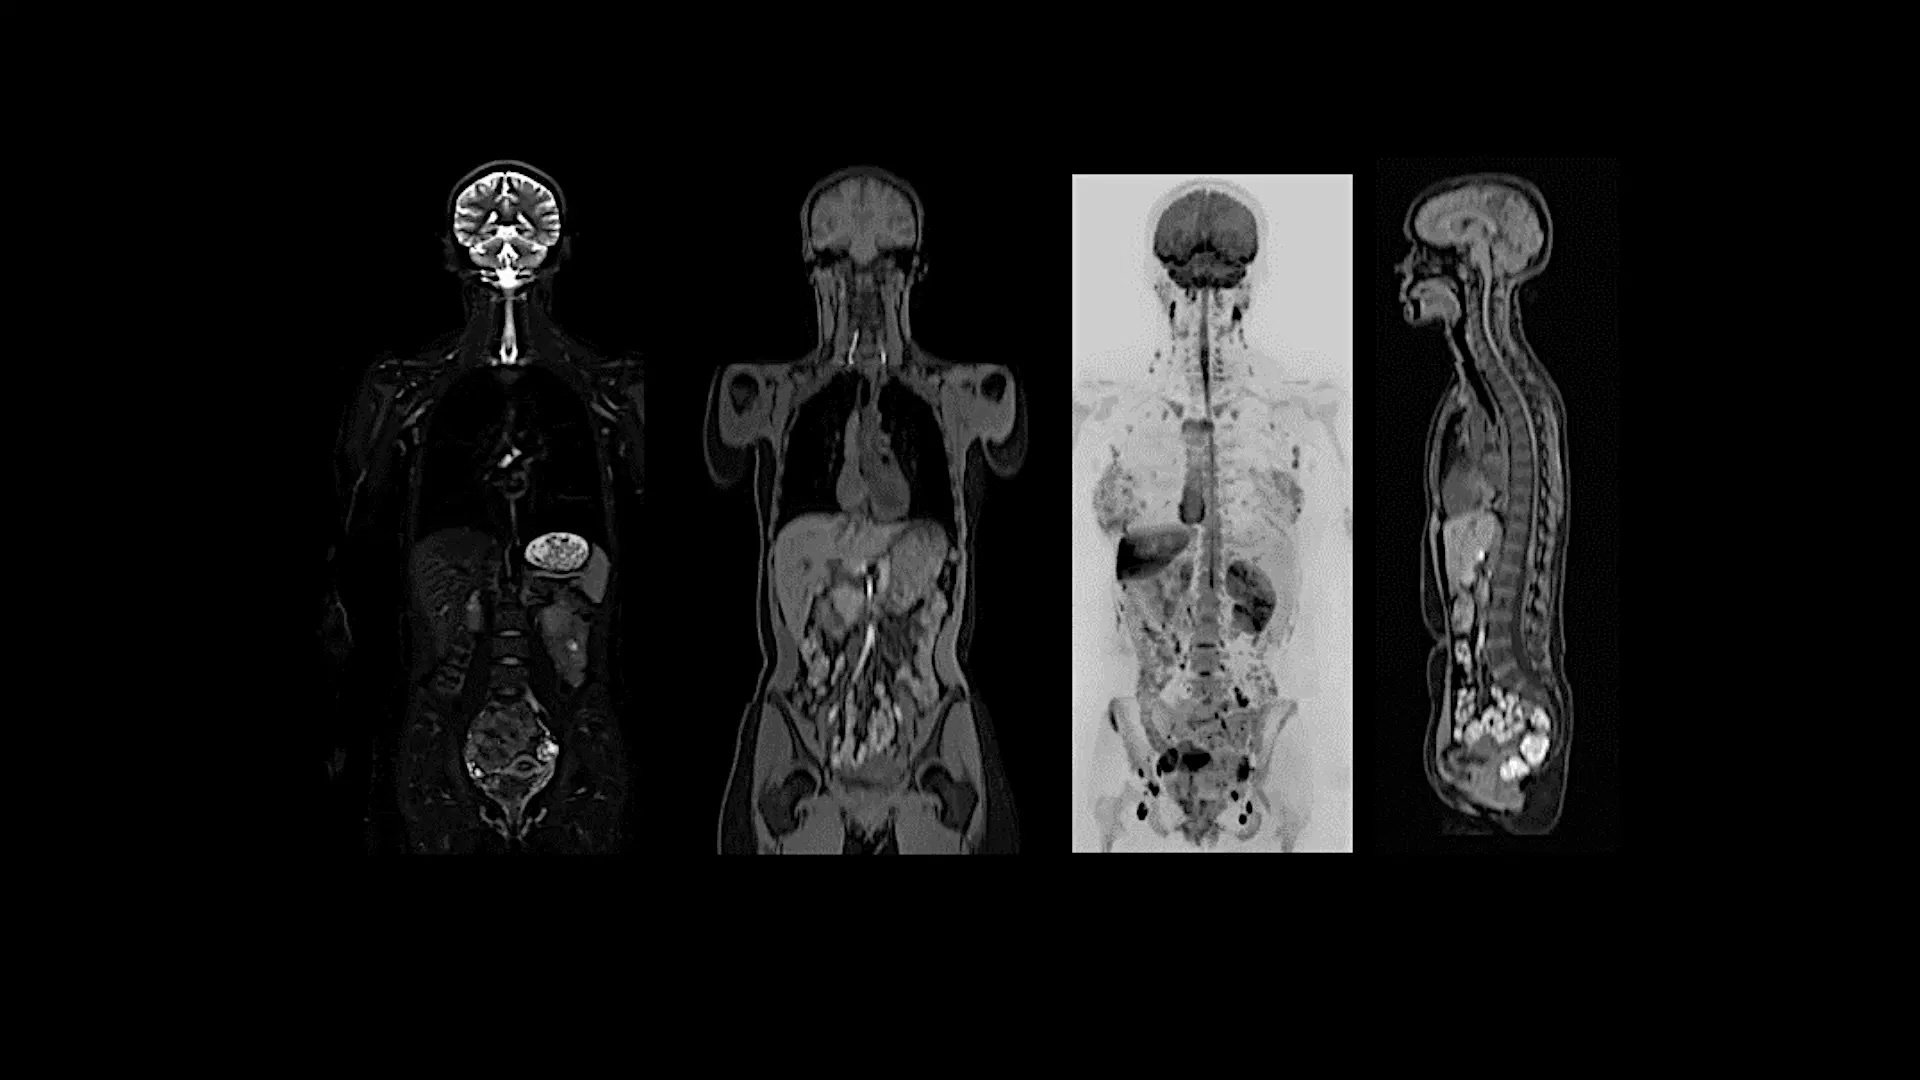

Whole Body

Whole body MRI exam with MET-RADs protocols

Study-ID:1aaaa5316. Acquired on MAGNETOM Flow. Platform with 70cm.

MAGNETOM Flow. Platform Whole Body